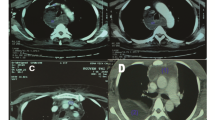

The 143 CTs were reviewed independently by three radiologists with fifteen, three, and one year(s) of experience in CT imaging. They looked for thoracic pathologies and recorded, if they were visible only above an imaginary plane at the tip of the diaphragm or if they were visible below as well (Fig. 2). All occurring pathologies are shown in Table 2. For all thoracic pathologies, which were visible only above the diaphragmatic dome, an intensive care physician (> 15 years of experience) determined retrospectively, if they were clinically relevant. Therefore, he searched our hospital information system for changes in patient management due to the pathologic findings on CT (only above the diaphragmatic dome).

In 143 CTs we found a total of 297 thoracic pathologies (median 2; IQR 1), see Table 2. More than two-thirds were pleural effusions and compression atelectases. In 29.4% of the CTs, patchy consolidations of the lungs compatible with the imaging diagnosis of pneumonia were found. In most cases, pathologic thoracic findings were visible below diaphragmatic dome. Only in 23 of 143 CTs we found thoracic pathologies, which were visible only above diaphragmatic dome (Fig. 3), so overall diagnostic efficacy of dedicated thoracic CT as part of the imaging protocol was 16.1% (95%-CI: 10.1–22.1%).

In five cases (3.5%) we found pneumonic infiltrates, which were visible only above diaphragmatic dome (Fig. 4 and 5). There were no other findings above the diaphragmatic dome, which could be reported as an infectious focus, so the diagnostic efficacy of thoracic imaging with regard to an infectious focus was 3.5% (95%-CI: 0.5–6.5%).